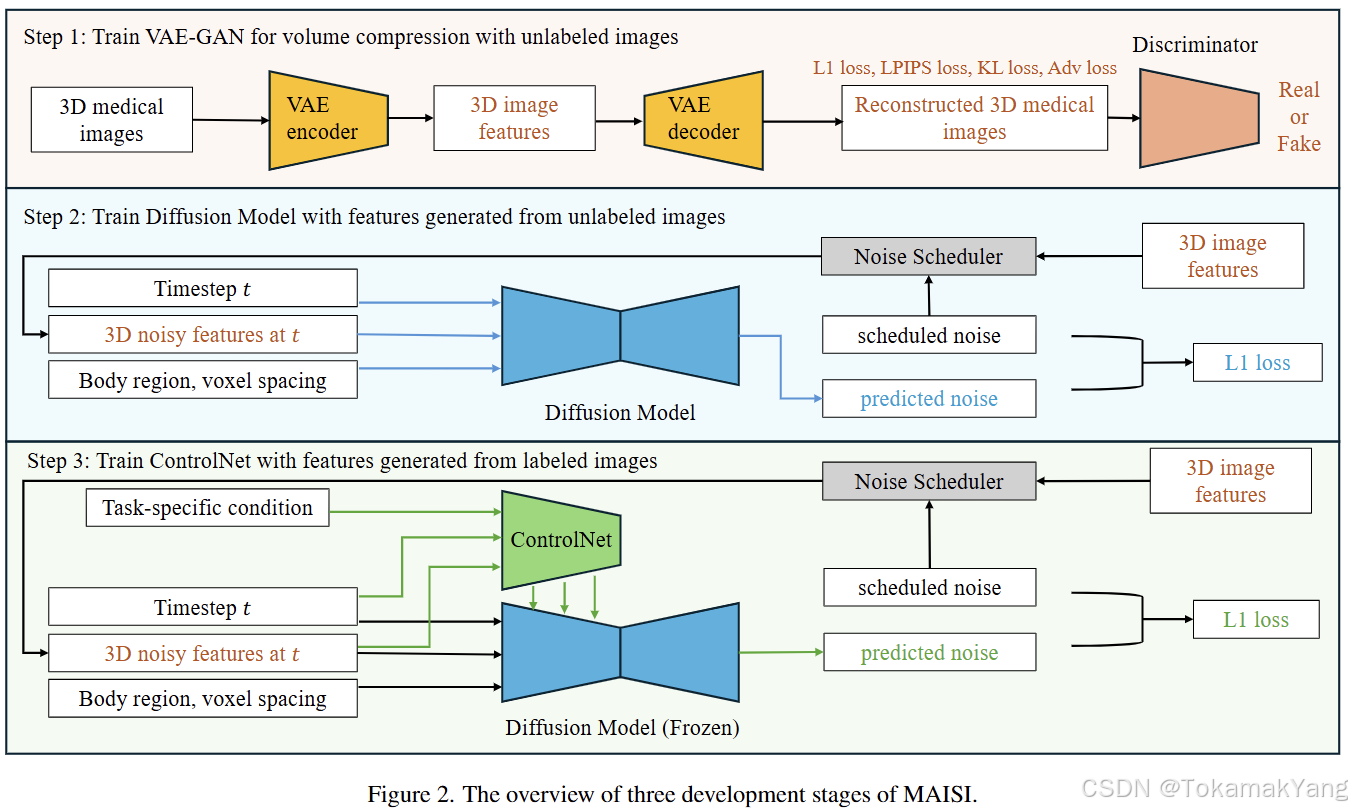

MAISI(Medical AI for Synthetic Imaging)是一种创新的基于扩散模型的方法,用于生成合成的3D计算机断层扫描(CT)图像,以应对上述挑战。MAISI利用基础体积压缩网络和潜在扩散模型,生成高分辨率CT图像,体积尺寸灵活,体素间距可调。通过引入ControlNet,MAISI能够处理包括127个解剖结构的器官分割图作为额外条件,生成带有准确标注的合成图像,适用于各种下游任务。

基础压缩网络采用变分自动编码器(VAE)训练,旨在将3D医学图像有效压缩到潜在空间中,并通过视觉编码器和解码器将生成的潜在特征映射回图像空间。为了减少内存占用,引入了张量分裂并行性(TSP),允许在统一的3D网络中对高分辨率CT体积进行编码和解码。

潜在扩散网络

潜在扩散模型在压缩的潜在空间中操作,以特定的身体区域和体素间距为条件,生成具有高度保真度的复杂解剖结构。该模型在来自不同数据集的10,277个体积上进行训练,涵盖各种身体区域和疾病条件,以增强其通用性和鲁棒性。

ControlNet支持额外条件控制

ControlNet被集成到MAISI框架中,提供了一种机制,可以在更广泛的动态控制下生成输出。它允许通过注入额外条件(如分割掩模、肿瘤掩模等)来控制生成过程,从而在不同任务或临床目标之间转换时,最小化对基础模型的广泛重新训练需求,节省时间和计算资源。